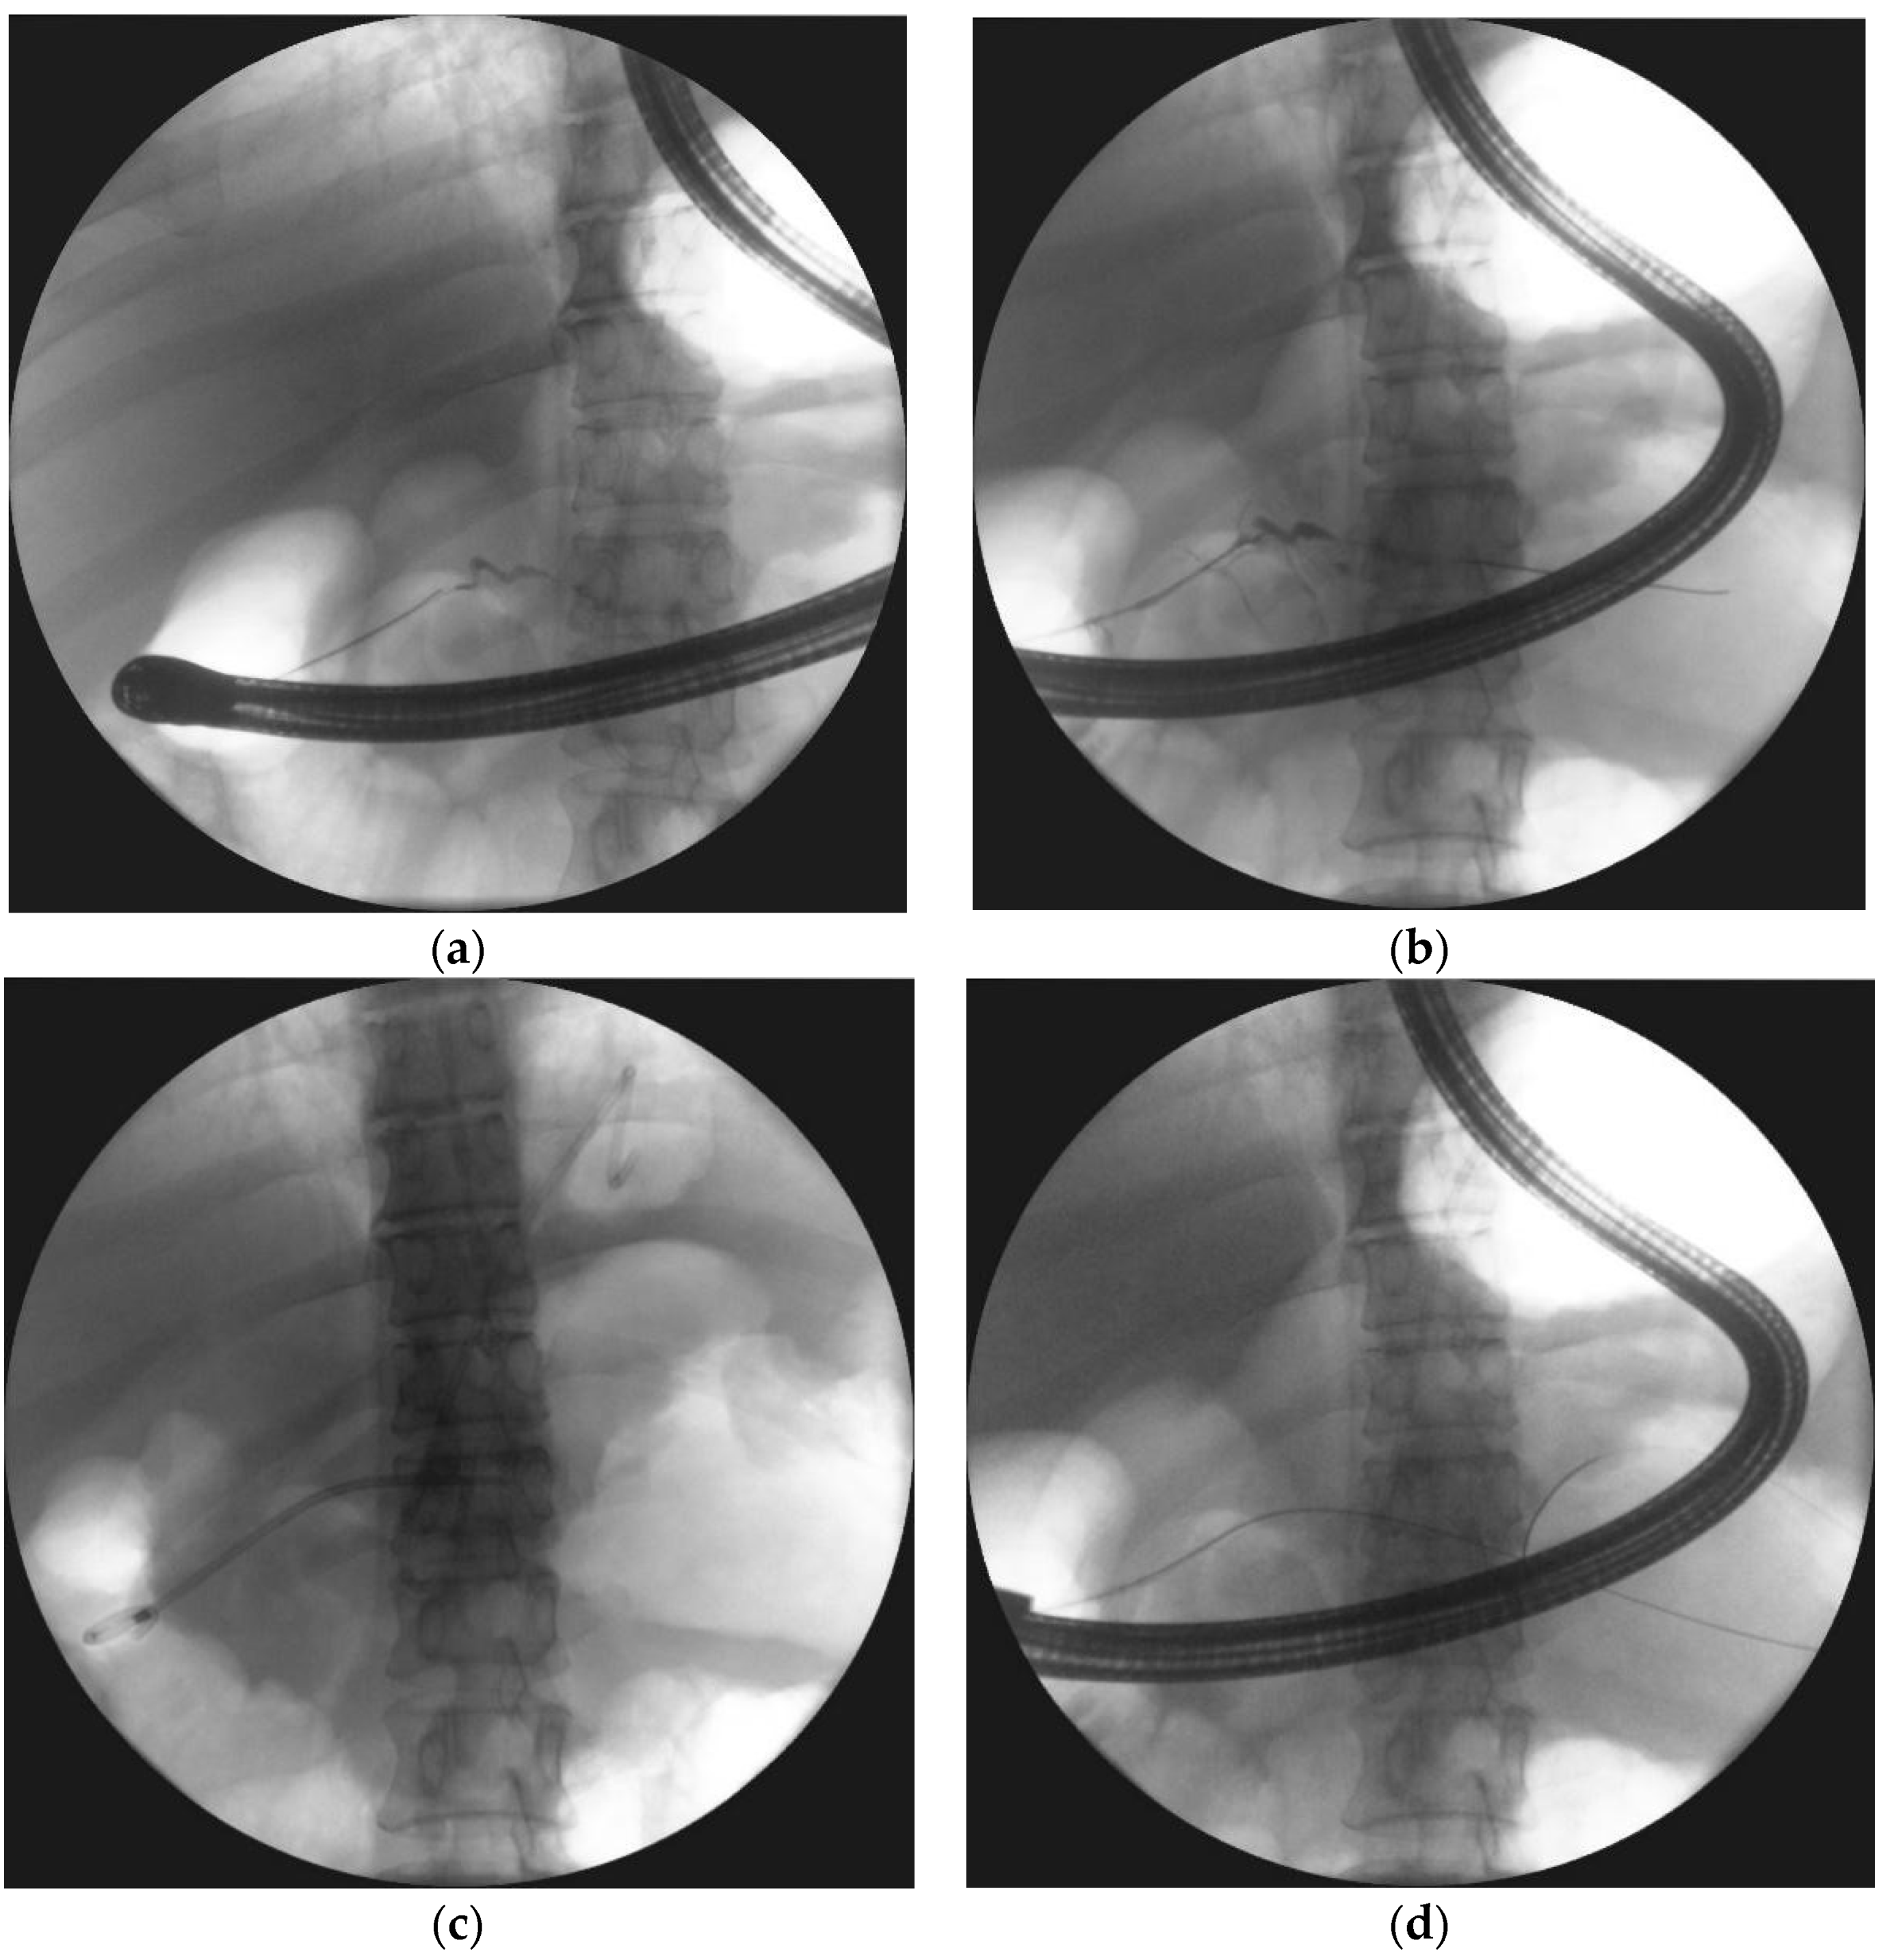

| Transmural endoscopic drainage with use of plastic stents | Active (with nasal drain) or passive (without nasal drain) transmural drainage enabled via insertion of plastic stent or stents through the transmural fistula into lumen of necrotic cavity. Mostly used in cases of well-liquefied collections of WOPN with small number of necrotic tissues in the lumen of WOPN, which usually take place after six weeks from the beginning of ANP. This type of drainage should be used in cases, where there is no necessity to perform endoscopic necrosectomy. |

| Transmural endoscopic drainage with use of SEMSs | Active (with nasal drain) or passive (without nasal drain) transmural drainage accomplished via insertion of metal stent (SEMS) through the transmural fistula into lumen of necrotic collection. Indications for this type of drainage are extensive WOPN containing poorly-liquefied necrotic tissues, in which endoscopic necrosectomy may be necessary in the next step. SEMSs are usually used in the endoscopic treatment of WOPN up to sixth week from the beginning of ANP. |

| Endoscopic necrosectomy under fluoroscopic guidance (endoscopic debridement) | Procedure that enable to remove necrotic tissues from necrotic cavity through transmural fistula under fluoroscopy with use of various types of endoscopic tools. Indication for endoscopic debridement is WOPN containing poorly-liquefied necrotic tissues. |

| Direct endoscopic necrosectomy | Procedure accomplished via insertion of endoscope through the transmural fistula into the lumen of WOPN and direct removal of necrotic tissues under endoscopic view with use of different types of endoscopic tools. Direct endoscopic necrosectomy is usually technically easier to proceed during transmural drainage with use of SEMSs. Indications for direct endoscopic necrosectomy are extensive WOPN containing poorly-liquefied necrotic tissues without clinical improvement despite active transmural drainage. |